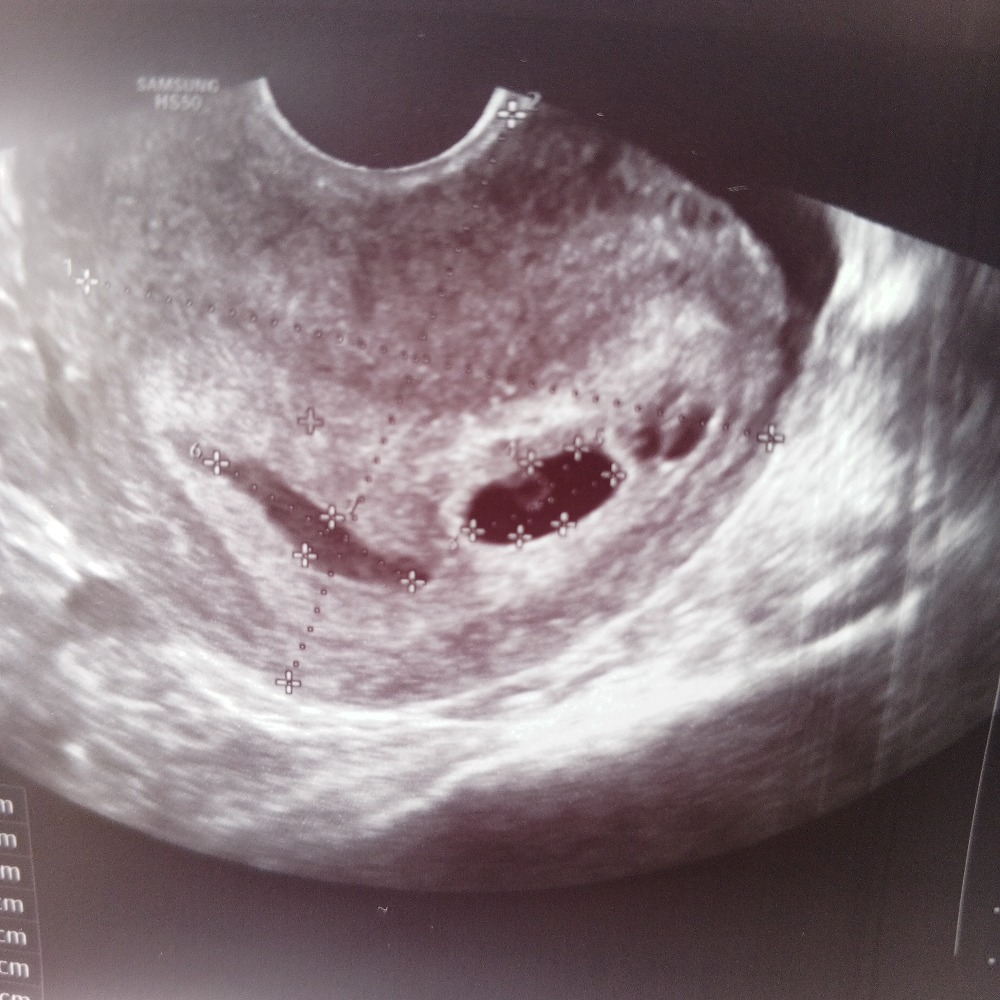

Такое большое пя, у меня вот первое фото там где-то 4.4 недели и второе фото через 9 дней где-то Изображение Изображение

Анастасия, понимаю, я в первый раз тоже из-за этого так как прихватило хорошо, а у вас думаю больше 5 недель, если даже эмбриончик определяется по снимку он беленькая точечка на желточном мешке, у вас я вижу